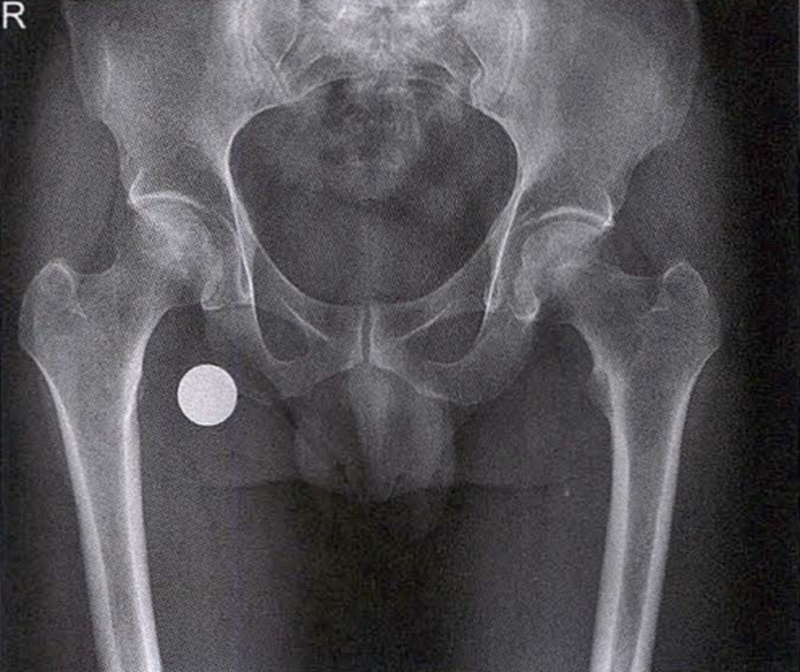

(1)X线检查 X线是诊断股骨头坏死的首选检查手段,常规拍摄髋关节正侧位片。早期股骨头坏死X线片可正常或显示股骨头外上方骨小梁稀疏;病情进展后逐渐出现密度增高、硬化带、囊性变等;晚期则出现股骨头塌陷、关节间隙变窄、Shenton's线不连续、骨关节炎改变等。硬化带和新月征是股骨头坏死X线特征性表现。在股骨头关节面塌陷变形早期上关节间隙不变或增宽后期随着骨关节炎加重关节间隙逐渐狭窄。

X线检查示右侧股骨头骨质密度不均匀